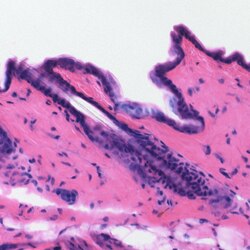

Drvna sječka stabla Haematoxylum campechianum. Hematoksilin u prahu. Koža miša, obojena s hematoksilinom (ljubičasta) i eozinom (ružičasta). Otopina hematoksilina.